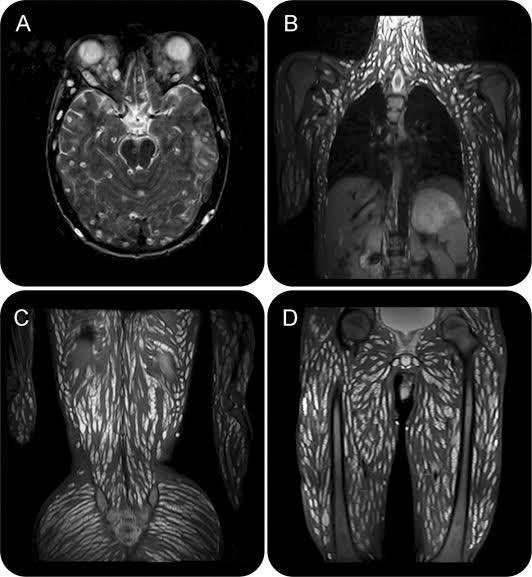

En la imagen se muestra la radiografía de un joven de 18 años, que acudió al médico por dolores de cabeza, vómitos, convulsiones frecuentes y alteración sensorial. En el examen presentó una extensa hipertrofia muscular.

Al realizar la resonancia magnética, se mostraron diferentes quistes en distintas etapas de los parásitos en el parénquima cerebral, cuero cabelludo, músculos extraoculares, el cuello, la pared torácica, la pared abdominal, los músculos paraespinales, glúteos, pélvicos y de la extremidades.

El paciente fue tratado con esteroides y fármacos antiepilépticos, consiguiendo recuperarse. Los expertos informaron que el paciente estuvo libre de crisis 6 meses después. En la neurocisticercosis diseminada, los síntomas se relacionaron con el efecto de ocupación de espacio más que con la inflamación provocada por los parásitos moribundos y, en esta situación, los fármacos cisticidas consiguen exacerbar el síndrome de hipertensión intracraneal.